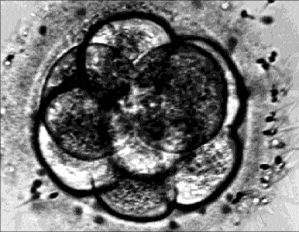

stem_cell_researchLa profesora emérita de la Facultad de Filosofía y Letras de la UNAM y ex directora de esa dependencia sostiene en su teoría que lo que fue el descubrimiento del secreto de la materia en el siglo pasado -cuando aconteció la gran revolución de la física-, hoy lo es en la biología, "el descubrimiento del secreto de la vida".